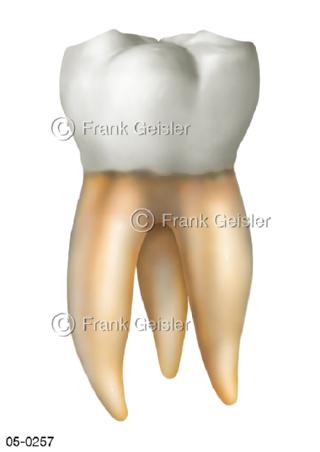

Bildergalerie Skelettsystem

Bilder zum Skelettsystem zeigen die Stützstruktur des menschlichen Körpers, die Knochen, eine besonders harte Form des Bindegewebes und Stützgewebes, welche das menschliche Skelett bildet, die Knochen des Stammes, der Extremitäten sowie der Gelenke